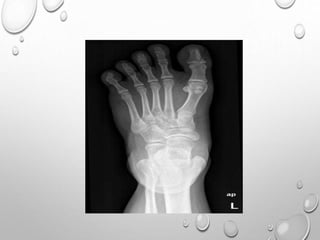

FIBRODYSPLASIA OSSIFICANCE

PROGERSSIVA

DISABLING GENETIC DISORDER OF CONNECTIVE TISSUE.

USUALLY SPORADIAC

MUNCHMEYER DISEASE

PRESENTATION : USUALLY DURING IST YEAR OF LIFE

CONGENITAL DIGITAL ANOMALIES

TORTICOLIS ( MOST COMMON C/F)

TRIVIAL TRAUMA – FEVER , INFLAMMATORY SOFT

TISSUE MASSES – PROGRESSIVE OSSIFICATION LEADING

TO RESTRICTED JOINT MOVEMENT

PATHOLOGY : LACK OF CIRCULATORY INHIBITORS OR PRIMARY

DEFECT IN COLLAGEN.

PAINFUL SOFT TISSUE MASS

COLLAGEN DEPOSITS ORGANIZE AND CALCIUM SALT

ACCUMULATE WITHIN IT.

LAMELLAR , WOVEN BONE FORMATION ….REPLACE

SMOOTH

MUSCLE, TENDON ,FASCIA ,LIGAMENTS

CONGENITAL DIGITAL ANOMALY

MICRODACTYLY OF IST TOE ..75% CASES , SOMETIME THUMB

( ABSENCE , SHORT PHALANX , SYNOSTOSIS)

HALLUX VALGUS

CLINODACTYLY

ECTOPIC OSSIFICATION

COLUMN OF BONES REPLACES LIGAMENTS , FASCIA , TENDONS

INTERVERTEBRAL DISC …HYPOPLASTIC , CALCIFIED

HYPOPLASTIC ANKYLOSED VERTEBRAL BODIES

(HYPOPLASIA DUE TO EARLY OSSIFICATIONOF SOFT TISSUE LEADS

TO PREMATURE FUSION OF CERVICAL GROWTH PLATE CENTERS)

BROAD FEMORAL NECK